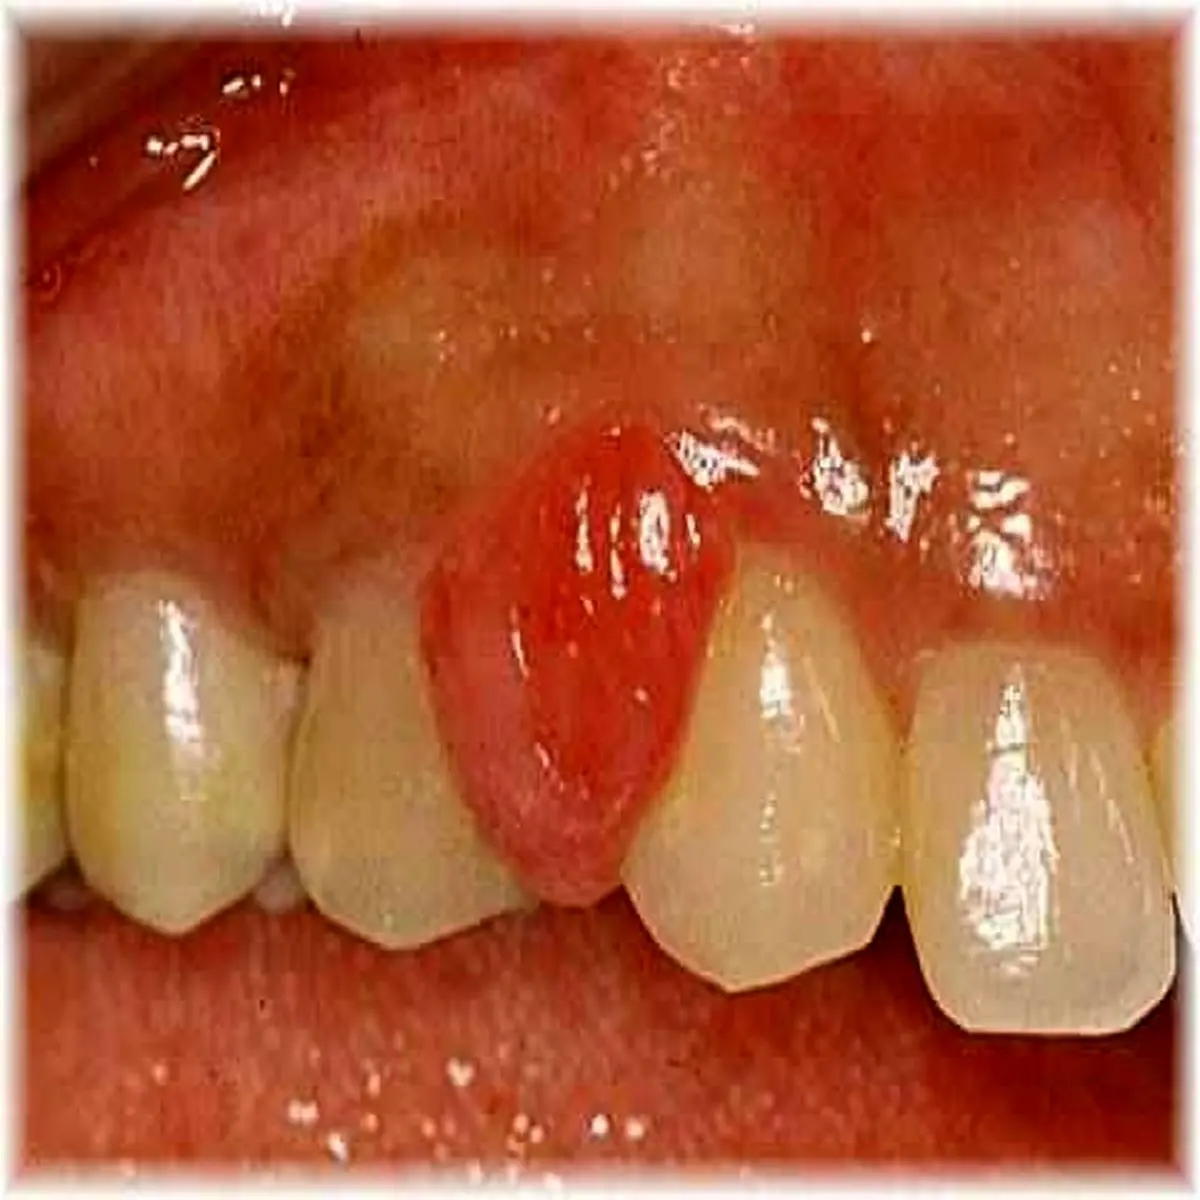

تومور حاملگی تومور بی ضرر و خوش خیمی دردهان است که در درصد کمی از زنان باردار ایجاد می شود. معمولا طی 3 ماهه ی دوم رشد می کند. ندول قرمز/ ارغوانی است که به طور معمول نزدیک لبه ی لثه ی دندان های بالا دیده می شود. گرچه در هر جای دیگری در دهان از جمله لب ها و زبان هم دیده شده است.این ندول به وسیله ی ساقه ی نازک بافتی به مخاط یا لثه متصل شده است.

تومور حاملگی التهاب و تورم قرمز رنگی است که دردهان یا روی لثه دیده می شود و اغلب با خونریزی و ناراحتی همراه است.

دندانپزشک در دوران بارداری دردهان شما به دنبال ندول قرمز و ملتهب و متورم می گردد. اندازه ی این ندول از چند میلی متر تا چند سانتی متر متغیر است. ممکن است خونریزی کند ، زخم بشود، پوسته پوسته شود. زنانی که از تومور حاملگی رنج می برند اغلب بهداشت دهانی ضعیف دارند و جرم زیادی در دهانشان تشکیل می شود.